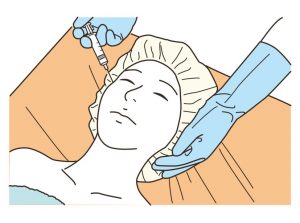

ショッピングリフト40本

やってきましたのでレポートです。

針をチクチク細かく刺しての施術

という事は、前もって知っていたので

ボトックスやヒアルロン酸の注入の

延長線上のような感じかなぁ?

と想像してましたが

案外、痛かったです( ; ; )

施術中

痛さを紛らわせる為か?

女性の先生がショッピングリフトの

魅力について存分に語って下さいながら

プスプス針を刺していく感じでしたが

残念ながら

話の内容が全く入ってこない(笑)

それくらい、痛かったです。